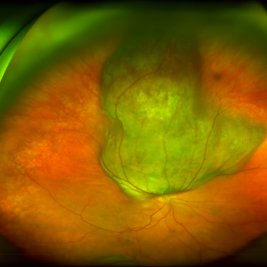

Large, Dome-Shaped Peripheral Choroidal Melanoma - Widefield Color

Large, Dome-Shaped Peripheral Choroidal Melanoma - Widefield Color

Feb 13 2020 by Michael Seider, MD

Large, dome-shaped peripheral choroidal melanoma of the left eye with inferior exudative retinal detachment. Note the lack of obvious orange pigment over the tumor and apparent drusen anteriorly. A lack of ophthalmoscopically obvious lipofuscin is not uncommon among larger choroidal melanomas. B-Scan ultrasonography (transverse, 10 o’clock) confirms a low-moderate internally reflective dome-shaped choroidal lesion with a small adjacent retinal detachment. Ultrasound biomicroscopy (radial, 10 o’clock) confirms no ciliary body involvement of the tumor.